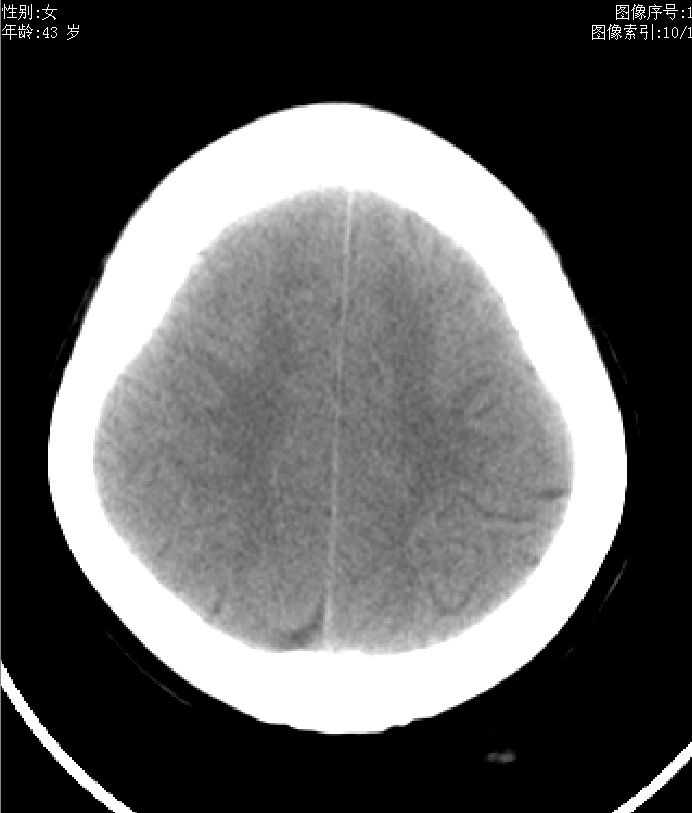

43岁,女性,头晕、语言含糊1天伴左侧肢体麻木,有高血压病史,bp160/100hg,余(-)。

蛛网膜囊肿

蛛网膜下腔囊肿

蛛网膜囊肿或脑沟。

蛛网膜下腔囊肿.